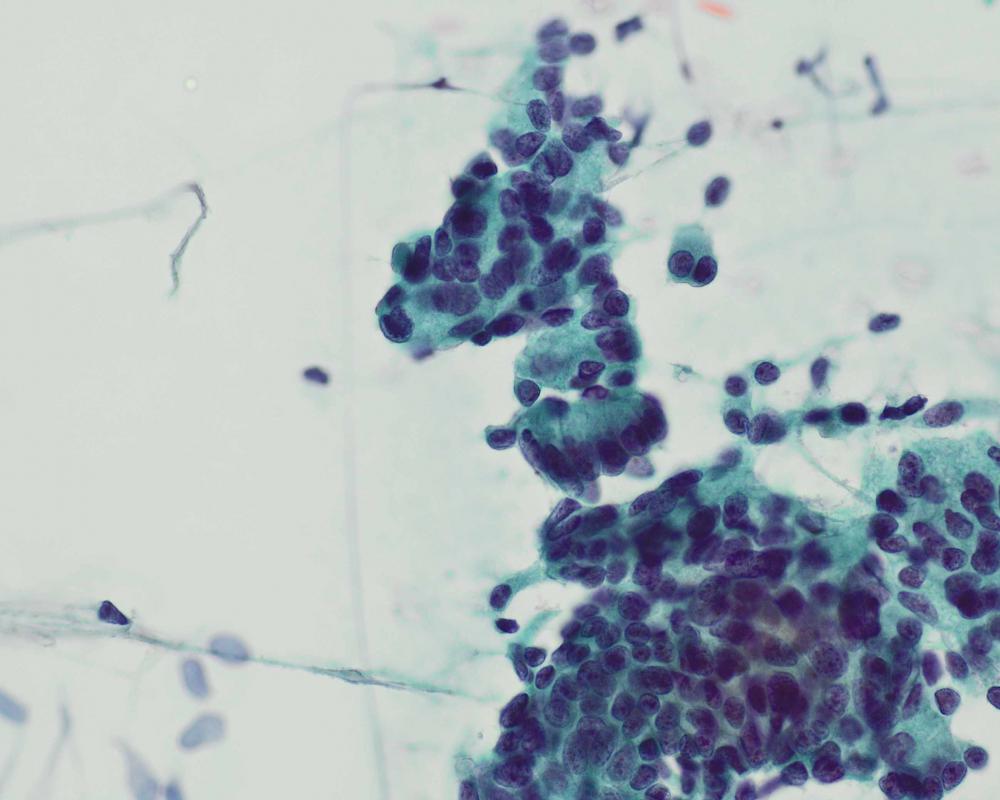

第37回日本臨床細胞学会九州連合会学会(佐賀)スライドカンファレンス症例5

種別:婦人科

出題:○大石 善丈 飯塚病院病理科

| 年齢 | 75歳 | 性別 | 女性 |

| 採取部位 | 子宮内膜 | 採取方法 | 擦過法 |

| 検体処理法 | 直接塗抹法 |

既往歴:10カ月前に右肺下葉腺癌にて右中下葉切除術。術後病理診断は乳頭型腺癌、pT2aN2M0 StageIIIA.

現病歴:肺癌の経過観察中、腫瘍マーカーのCEAが上昇したためPETを施行され、子宮体部に異常集積が認められた。子宮体癌が疑われ、内膜細胞診が提出された。

| 正解 | 4.肺腺癌の子宮転移 |

| 1.類内膜癌 | 15件 | (18.8%) | |

| 2.漿液性腺癌 | 10件 | (12.5%) | |

| 3.子宮内膜異型増殖症 | 0件 | (0.0%) | |

| 4.肺腺癌の子宮転移 | 30件 | (37.5%) | |

| 5.中腎管様腺癌 | 25件 | (31.2%) | |

| 投票総数 | 80件 | (100%) |